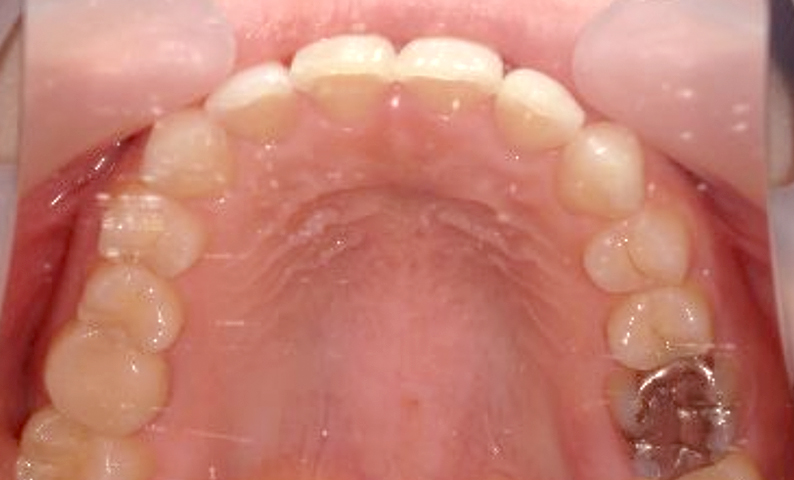

症例_024 上顎だけの部分矯正

治療期間:7ヶ月金額:30万円+税女性前歯のガタガタ上の前歯だけ

| Before | After |